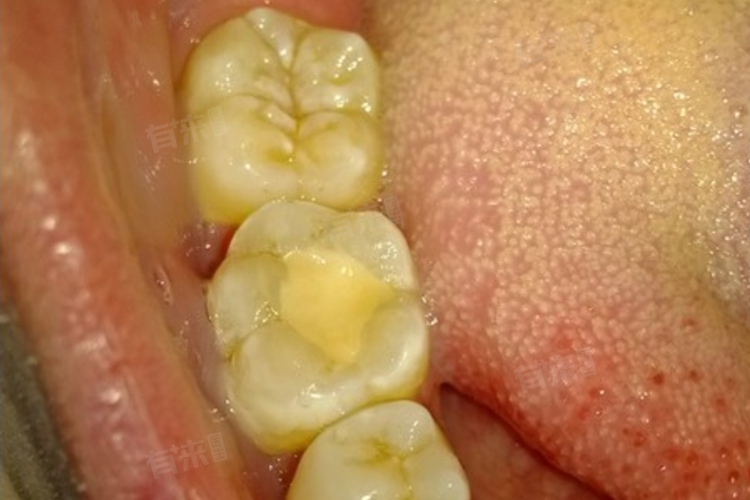

2、嵌体修复:若原补牙位置龋坏面积扩大,或牙体缺损较多,适合嵌体修复。制取牙齿模型定制瓷嵌体或树脂嵌体,将其精准嵌入牙洞,通过粘接固定。嵌体与牙体贴合紧密,耐磨且不易脱落,能有效恢复牙齿咀嚼功能。